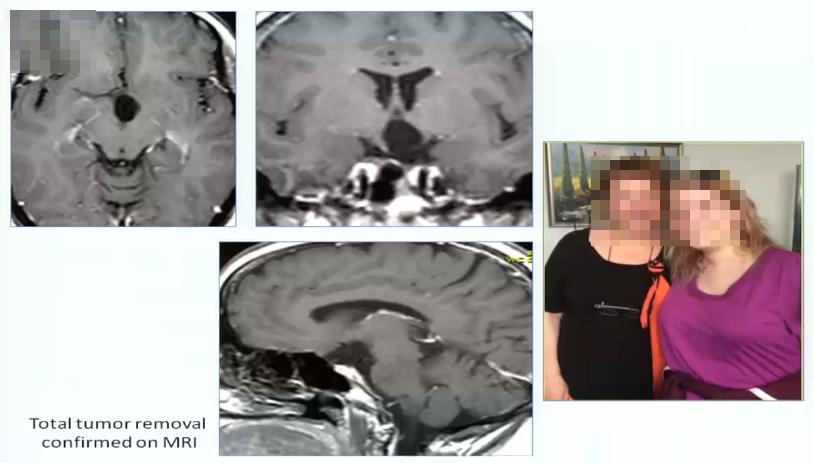

视路胶质瘤全切手术病例1:

24岁女性、闭经,胶质瘤主要累及下丘脑

术中情况: 患者视路、视交叉肿胀非常明显。接下来显示通过翼点入路视角处理丘脑胶质瘤的情况。直接切开视交叉部位,然后打开中板,松解嗅神经,否则会因牵拉额叶造成嗅神经嗅丝断裂。三室完全被肿瘤充满,好消息是肿瘤和脑室壁有很好的界限。瘤脑界面清楚,肿瘤大部分清除,先做活检。做完活检,然后kusa进行肿瘤大部分减容,一定要分离的时候牵拉轻柔,不要把肿瘤夹得过碎,以方便大块切除。1.4mm 检查周围穿支保留及是否有肿瘤残留,一定要仔细检查瘤仓的各个角落,确保没有残留。

术后情况: 肿瘤全切,患者情况良好。